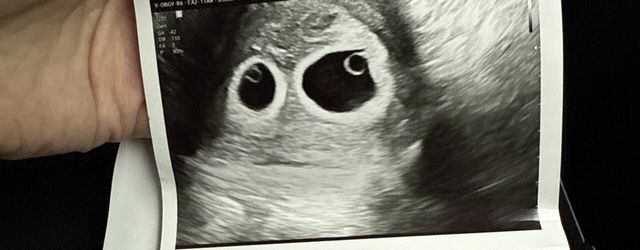

시험관 2년 도전만에

드디어

이제 12주 되었습니다